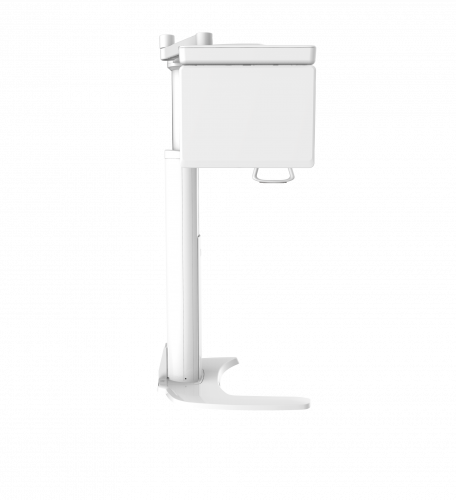

| TYPE | TOP VIEW | FRONT VIEW |

|---|---|---|

|

PaX-i (Pano) |

|

|

|

PaX-i SC (Pano/Scan Ceph) |

|

|